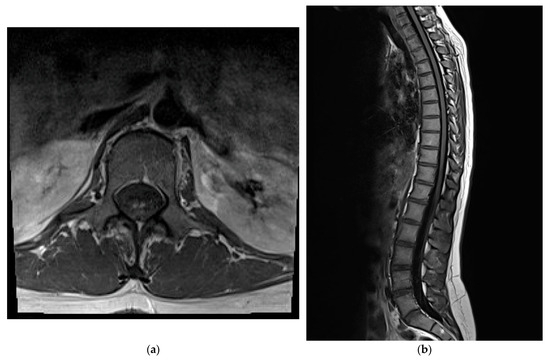

A follow-up MRI of the thoracic and lumbosacral spine revealed multiple small T2-hyperintense intramedullary lesions, the most prominent from T9/T10 to T11/T12, involving mainly the posterior spinal cord. At T12/L1 to L1/L2, symmetrical foci were seen in both the anterior and posterior horns, forming the characteristic “snake eye” sign. The post-contrast images showed an enhancement of the cauda equina nerve roots. No compressive lesions or vertebral abnormalities were present. The distribution and intensity of the lesions were stable compared to the prior scans and suggested an inflammatory or autoimmune etiology (Figure 1). Based on the clinical presentation and MRI findings, a diagnosis of acute transverse myelitis was confirmed, and therapeutic plasmapheresis was commenced. The patient underwent a total of five sessions of plasma exchange, resulting in a partial clinical improvement, including a reduction in paresthesias and a gradual return of motor strength.

The diagnosis of ATM was ultimately supported by the patient’s clinical profile, MRI findings, and a partial response to the immunomodulatory therapies. The longitudinally extensive lesion involving the posterior columns of the thoracic cord, observed in the T10–T12 region, correlated well with her sensory and motor deficits. It is worth noting that posterior column involvement typically results in proprioceptive loss and gait ataxia, which were among the patient’s initial symptoms. The absence of brain lesions on the MRI supported the exclusion of multiple sclerosis (MS), while the lack of oligoclonal bands in the CSF and negative anti-AQP4 and anti-MOG antibody results argued against neuromyelitis optica spectrum disorder (NMOSD) [8].

Figure 1. Magnetic Resonance Imaging (MRI) of the spine (T2-weighted). (a) Axial view of the spinal cord showing the “snake eye” sign. (b) Sagittal view with longitudinal T2-hyperintense lesions from T9 to L2 affecting posterior columns.